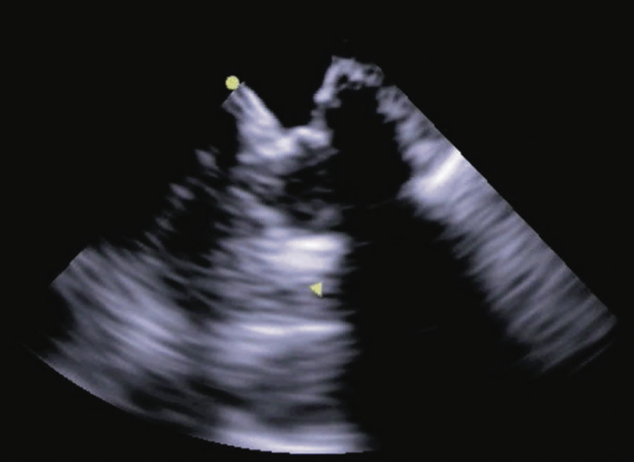

In early 2020, we began adopting preprocedural CT angiography imaging prior to our scheduled LAA closure case days to facilitate same-day discharge, eliminate the use of general anesthesia, and incorporate intracardiac echocardiography (ICE). We are increasingly using ICE during EP procedures to view cardiac structures, guide transseptal catheterization, evaluate the position of ablation catheters, assess for occlusion of the pulmonary vein during cryoballoon ablation, and exclude complications such as pericardial tamponade and thrombus formation.5 TEE can also be used to guide cardiac interventions and is commonly used during structural heart procedures such as percutaneous valve interventions and LAA closures. One major disadvantage of using a TEE probe to guide EP procedures is the need for and complications associated with general anesthesia in the elderly population. Over the last 3 years, we have been using a 2D ICE catheter placed in the left atrium to guide LAA closures.6 In addition, we very recently began using a four-dimensional (4D) ICE catheter to guide LAA closure, and present a brief case below (Figure 1). We are also excited about the possibility of newer ablation modalities such as pulsed field ablation.

Case Presentation: LAA Closure Using 4D ICE

A 78-year-old female with a significant past medical history of permanent nonvalvular AF, hypertension, diabetes, and vascular disease was recently referred for LAA closure. She suffered from esophageal strictures and a large hiatal hernia. Due to her comorbidities, the patient was not ideal for long-term anticoagulation. Therefore, it was determined to proceed with conscious sedation and ICE for Watchman device (Boston Scientific) implant. CT angiography prior to the scheduled procedure was obtained for sizing as well as for guiding transseptal puncture. Precise measurement of the landing zone was performed using the ACUSON AcuNav 4D Volume ICE Catheter and ACUSON SC2000 PRIME ultrasound system (Siemens Healthineers), and the Watchman device was implanted with no complications. The groin was closed using a figure-of-8 stitch and the patient was placed on 3-hour bedrest. Once the suture was removed from the groin and the patient demonstrated appropriate hemostasis of the groin, the patient was discharged from the hospital on the same day of the procedure.